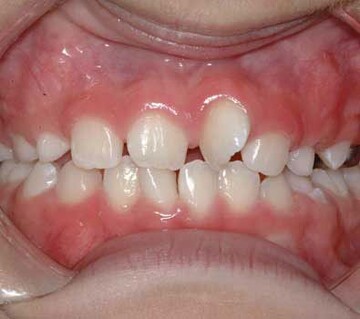

One of our most common consults occurs when children around the age of 7 begin to lose their lower front teeth. Many of our parents become overly worried about this phenomenon. It is VERY NORMAL for permanent lower incisors (front teeth) to erupt behind their predecessors (baby teeth), however if a baby tooth is not loose by the time half of the permanent incisor has erupted, it may be necessary to pull it.